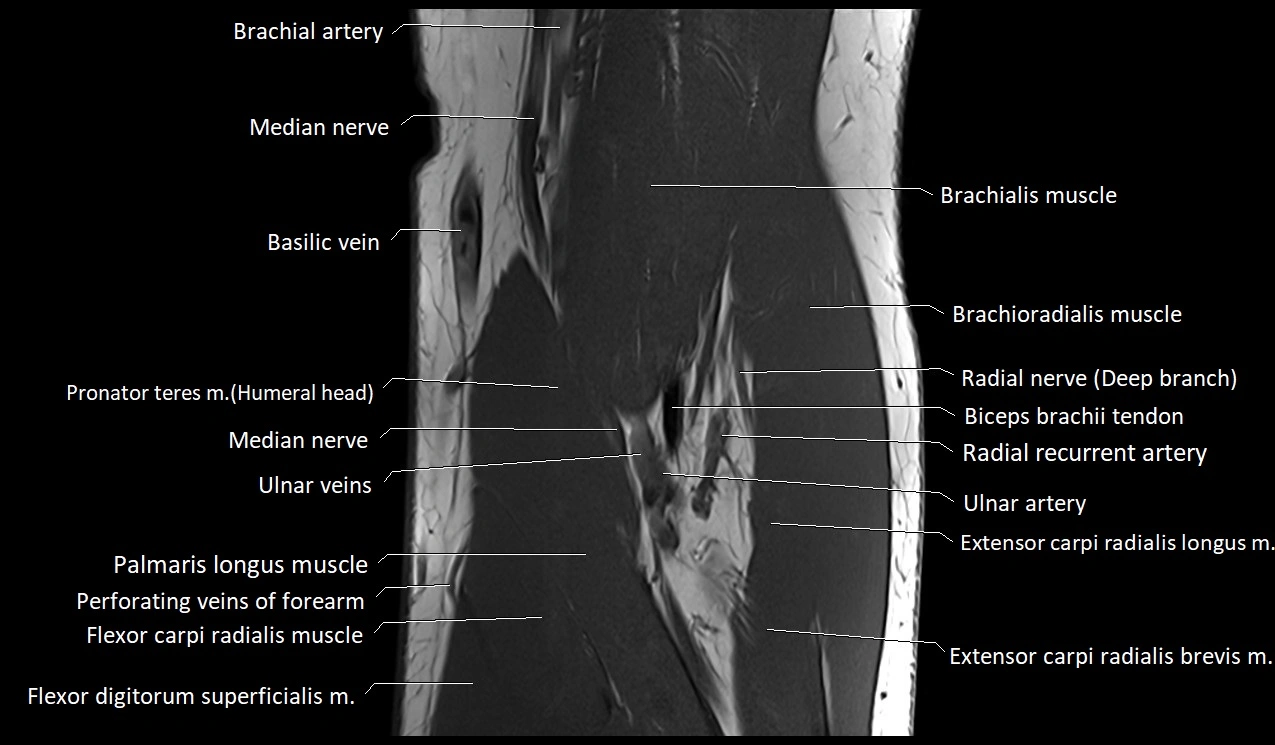

MRI image

image